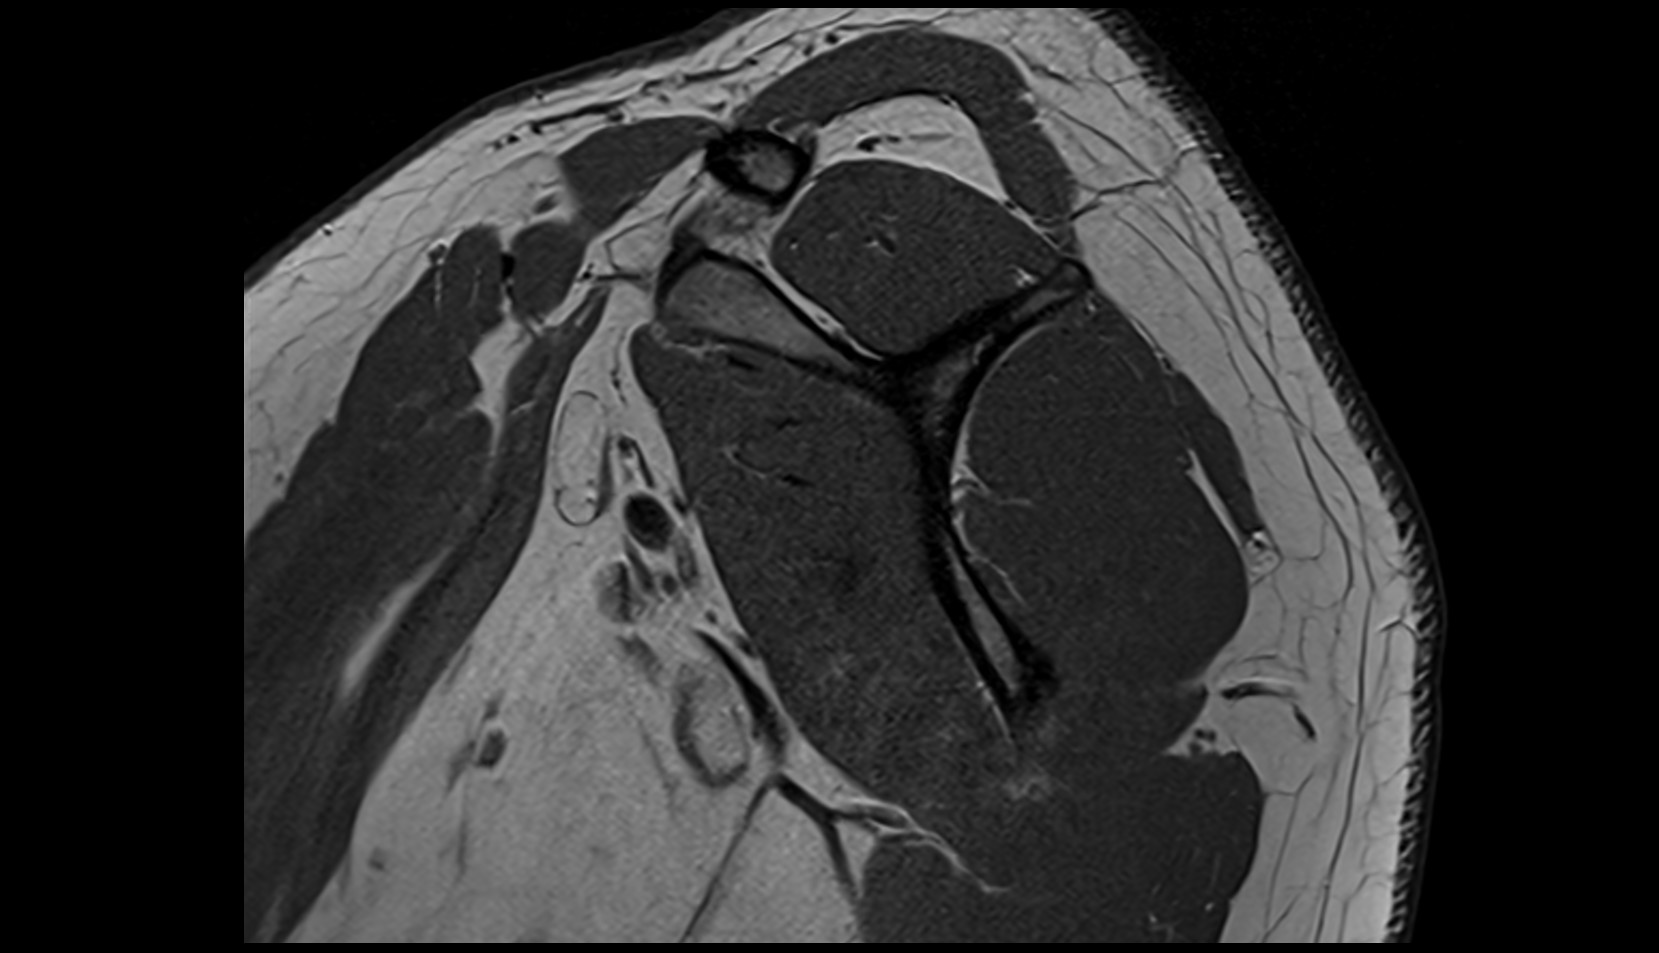

- Shoulder joint (glenohumeral joint)

- Glenoid labrum

- Glenohumeral joint capsule

- Supraspinatus tendon

- Infraspinatus tendon

- Subscapularis tendon